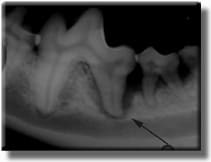

Radiograph reveals severe bone loss and an abscessed tooth hidden beneath the gumline.

Half of the lower jaw bone has been destroyed by infection under the gum line, and the tooth required extraction. This process took years to occur, but was hidden under the gum line, out of view. If this had been caught sooner, the tooth could have been treated.